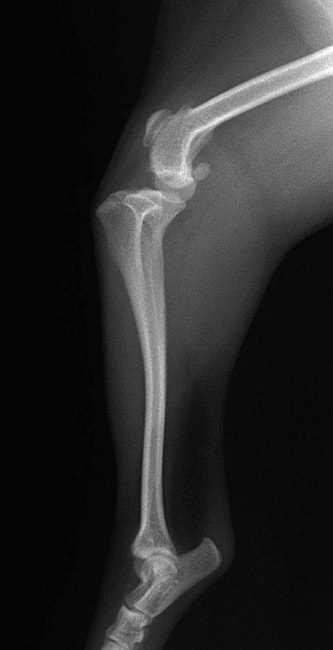

■ 症例20 ポメラニアン 8ヶ月 1.8kg

左右膝蓋骨脱臼 グレードⅢ

2ヶ月前から間欠的跛行が認められ、両膝の膝蓋骨脱臼整復術を行った。

手技は縫工筋及び内側広筋の解放、脛骨粗面の外側転位、滑車ブロック形造溝術、内外側関節包の縫縮を選択し実施した。

右側の膝蓋骨脱臼は上記手技で整復されたものの、左側はそれのみでは膝蓋骨が浮く様子が認められた。その為、PDS縫合糸にて膝蓋靱帯を1糸のみ縫合し、靱帯の縫縮を行った。

膝蓋骨脱臼は膝関節における膝蓋骨の内外側の脱臼と定義されるが、時として単純な内外の脱臼ではなく、膝蓋骨が大きく前方に浮き上がるように脱臼する場合がある。特にトイプードルやポメラニアンといった犬種に多く認められる。

内側脱臼に加えて前方への浮き上がりを矯正する為に、従来より脛骨粗面転移により膝蓋靭帯を外方と下方に引っ張り、固定する方法を選択する。膝蓋骨の前方への浮き上がりが軽度の場合は、従来法ではなく関節包の縫縮で対応していた。しかし、一部の症例で膝蓋骨の動きが悪くなり伸展機構が円滑に機能せずロボット様歩行になるケースがあった。

その為、膝蓋靭帯自体を縫縮する方法を採用した。この方法により、膝関節の伸展機構を妨げず膝蓋骨の軽度の浮きを矯正することが可能となった。

本症例の経過は良好である